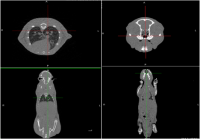

Super Nova系统扫描小鼠CT图像

Super Nova系统CT扫描实验鼠三维图像